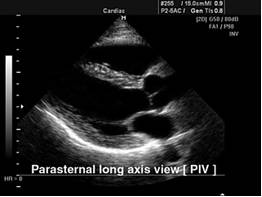

Диагностика пороков клапанов сердца

Зачастую пациенты узнают о проблемах с клапанами сердца после полноценного, адекватного осмотра врача, который в процессе аускультации выявил шумы в сердце, после чего пациенту назначается ряд исследований, имеющих разную диагностическую ценность:

- чреcпищеводная эхокардиография (более сложное и более дорогое исследование);

- ЭКГ;

- трансторакальная эхокардиография (УЗИ сердца) – наиболее информативный, распространенный и недорогой способ диагностировать патологию клапанного аппарата сердца;

- аортовентрикулография;

- рентгенография органов грудной клетки;

- мультиспиральная компьютерная томография с контрастированием.